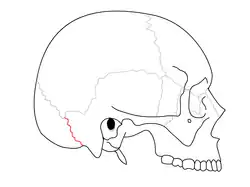

Suturas

Sutura occipitomastoidea separa o osso occipital do mastoide do osso temporal.

Sutura occipitomastoidea separa o osso occipital do mastoide do osso temporal. -

Vista lateral do crânio.

Vista lateral do crânio. -